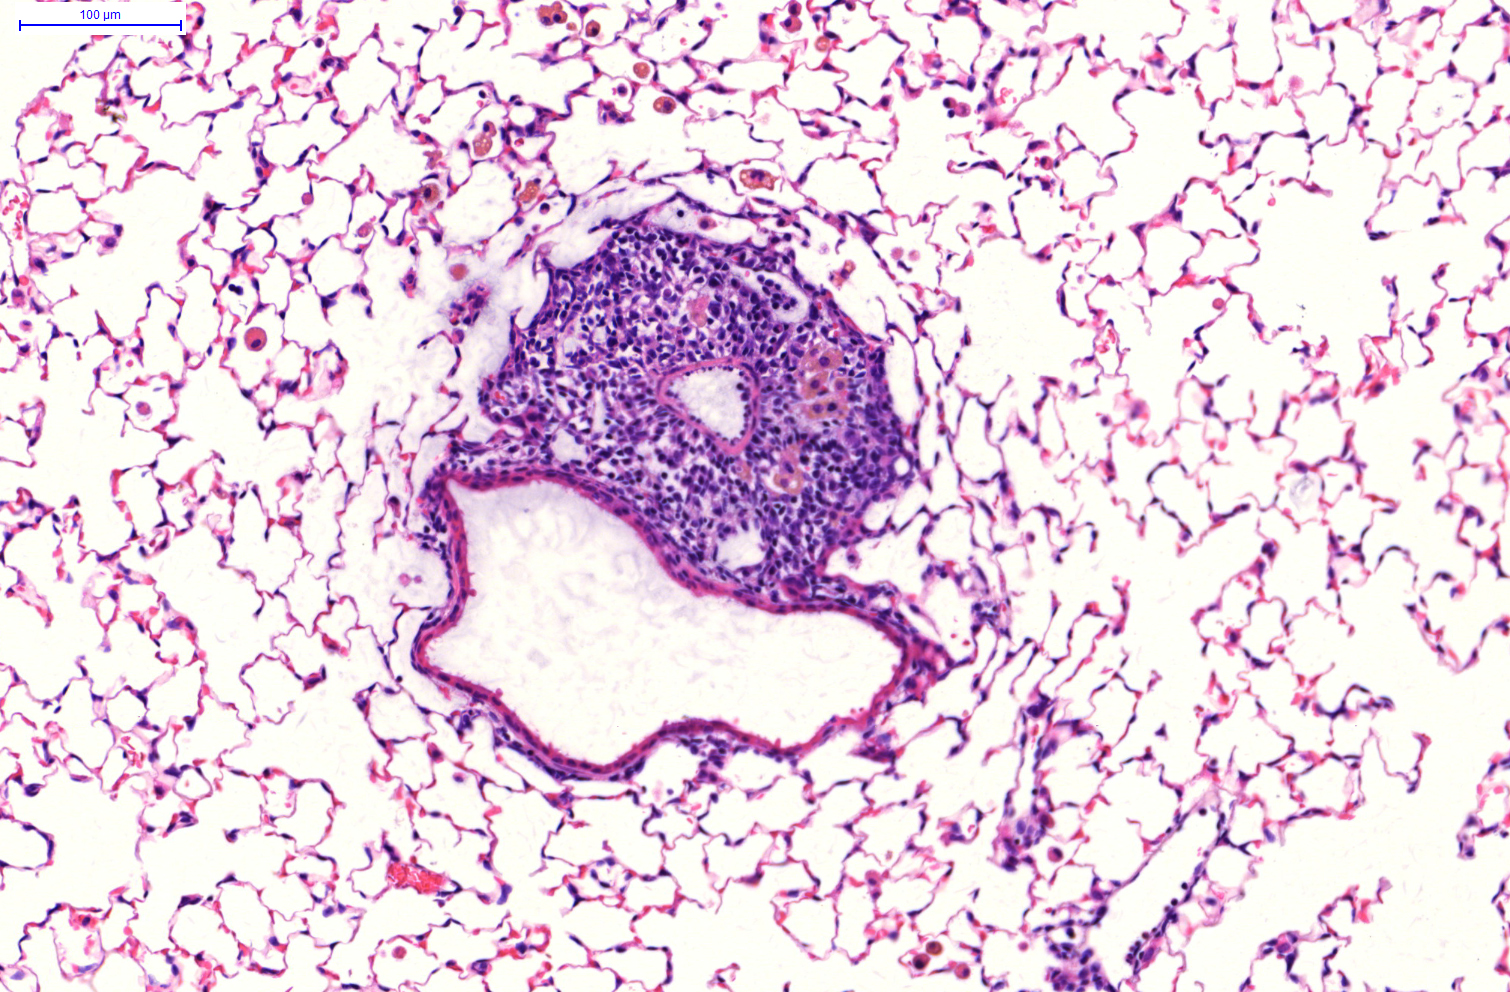

In a recent paper, a team led by Dr. Ali Önder Yildirim shed new light on the inflammatory process. “We focused on tertiary lymphoid organs* in the bronchi,” explains Yildirim, one of the acting directors of the Institute of Lung Biology at Helmholtz Zentrum München, a member of the German Center for Lung Research (DZL). Specifically, the researchers studied what is known as inducible bronchus-associated lymphoid tissue, or iBALT for short. “It is believed that the development of iBALT plays a key role in the deterioration of COPD − but until now it was unclear exactly how iBALT forms,” says the head of the study.

“We wanted to find out whether that is also the case around the lungs and specifically in cigarette-smoke-induced COPD,” Yildirim says. In fact, the researchers found elevated levels of enzymes involved in oxysterol metabolism together with immune cells that migrate into the tissue both in the experimental model and in the lungs of COPD patients. Further experiments also showed that iBALT formation is inhibited if the metabolic enzymes are absent. Their absence also prevented the migration of immune cells and damage to the lungs despite exposure to cigarette smoke.